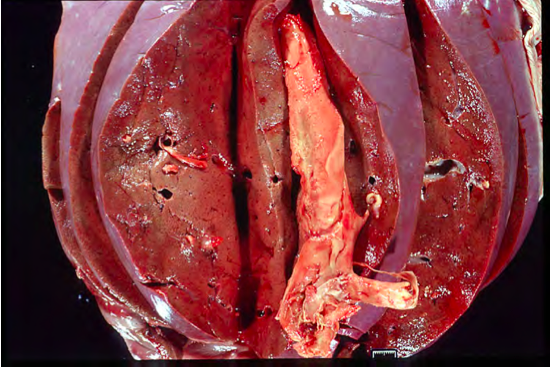

MASSIVE HEPATIC NECROSIS IN HEPATOSIS DIETETICA OF SWINE. CUT SURFACE

One of the most common causes of massive hepatic necrosis is the condition known as hepatosis dietetica of swine.

Hepatosis dietetica has been associated with generation of free radicals and deficiency of Vitamin E/Selenium.

Involves entire lobule or contiguous lobules

Although this type of necrosis is commonly severe, the name massive indicates involvement of the whole lobule.